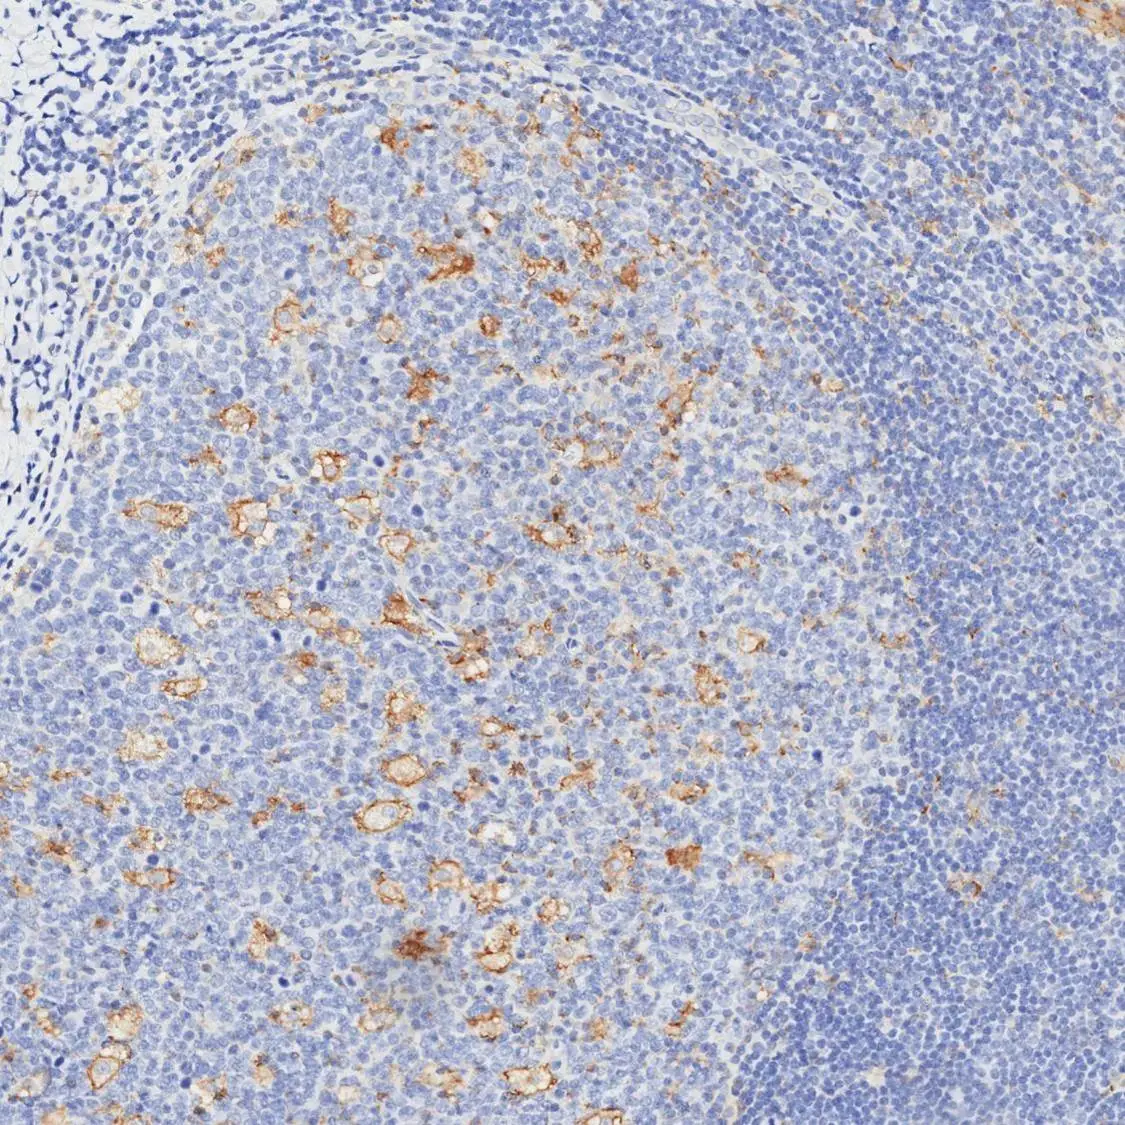

Optimal staining result of human tonsil using PD-L1 antibody [H302] HistoMAX™ on Leica Bond III, following the vendor recommended protocol settings.

Distinct punctate membranous reactivity (weak-to-moderate intensity) observed in germinal center macrophages and scattered lymphocytes. Note the high signal-to-noise ratio, with the predominant lymphocyte population remaining non-reactive.